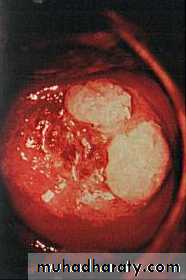

Cervical warts